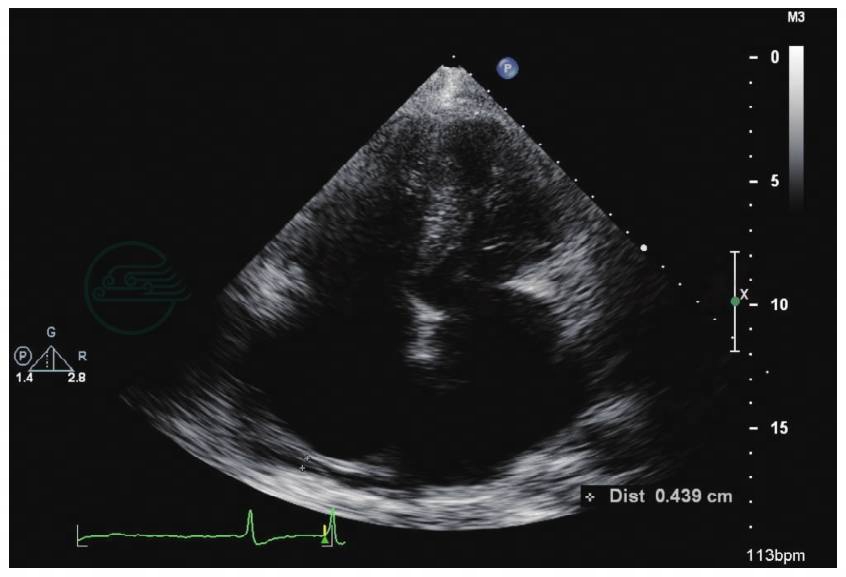

3.超声心动图(图3、图4)

图3 超声心动图(左室长轴):左室内径47mm,室间隔增厚约19mm

图4 超声心动图(心尖四腔图):双房显著扩大

超声心动图所见心肌病变的特点是既有心肌肥厚的表现,又有限制型心肌病的表现,特别是心尖四腔位切面所见左心室不大,双房高度扩大,下腔静脉增宽,强烈提示限制性血流动力学改变的特点。而超声心动图所见排除了原发的瓣膜病变。为进一步明确心脏病的性质和特点进行了心脏MRI和MDCT检查。